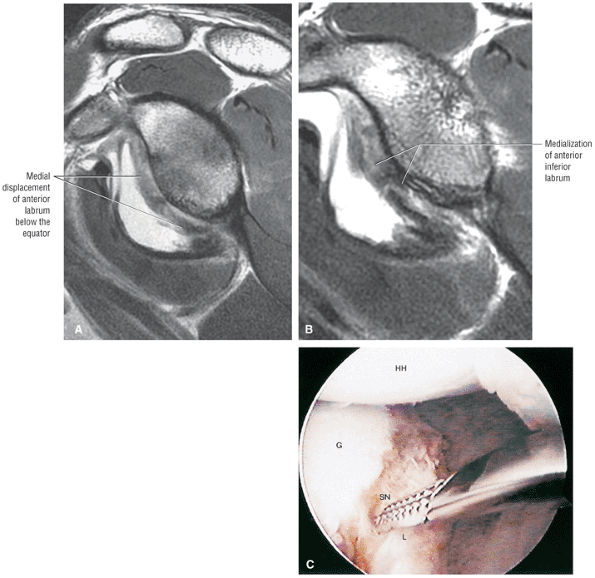

FIGURE 8.102 ● (A) The anterior undersurface of the acromion and the coracoacromial ligament form the coracoacromial arch. The subacromial subdeltoid bursa facilitates the passage of the rotator cuff and proximal humerus under the coracoacromial arch. (B) A superior axial image shows the anterior-to-posterior extent of the coracoacromial (CA) ligament perpendicular to the supraspinatus tendon. The fluid in the subacromial-subdeltoid bursa represents fluid between two serosal surfaces in contact with each other. One serosal surface is contributed by the undersurface of the coracoacromial arch and deltoid, and the other serosal surface is on the bursal side of the cuff.

|

![]() |

FIGURE 8.103 ● Pseudospur. The normal broad attachment of the coracoacromial ligament to the inferior surface of the acromion is shown on (A) T1-weighted coronal oblique and (B) sagittal oblique images. The low-signal-intensity acromial cortex (black arrows) and adjacent coracoacromial ligament and lateral slip of the deltoid attachment (white arrows) give the false impression of a small subacromial spur in the coronal plane. This pseudospur should not be misinterpreted as impingement; otherwise, unnecessary acromioplasties may be performed on patients with a normal coracoacromial ligament attachment and no associated acromial spurs.

-

Impingement syndrome, a clinical diagnosis, is characterized by a range of MR findings from tendinosis to rotator cuff tears.

Intrinsic impingement is associated with shoulder instability.